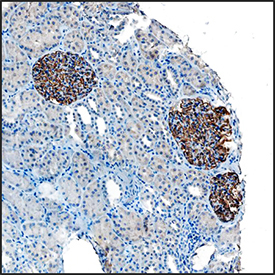

- Main image

- Experimental details

- Synaptopodin in Human Kidney. Synaptopodin was detected in immersion fixed paraffin-embedded sections of human kidney using Mouse Anti-Human Synaptopodin Monoclonal Antibody (Catalog # MAB8977) at 15 µg/mL overnight at 4 °C. Tissue was stained using the Anti-Mouse HRP-DAB Cell & Tissue Staining Kit (brown; Catalog # CTS002) and counterstained with hematoxylin (blue). Specific staining was localized to glomeruli. View our protocol for Chromogenic IHC Staining of Paraffin-embedded Tissue Sections.